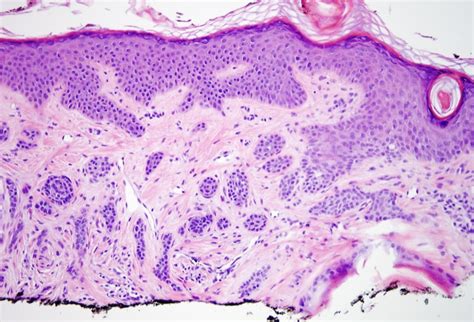

Webpathology.com: A Collection of Surgical Pathology Images

Webpathology.com: A Collection of Surgical Pathology Images from www.webpathology.com